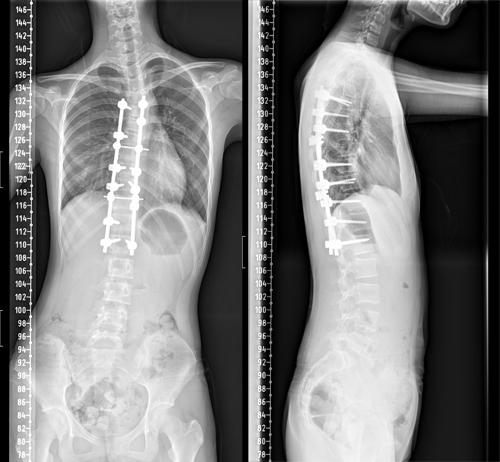

术后护理团队制定了详细的护理计划,严密观察患者生命体征及切口情况。在科室全体医护人员的共同努力下,小冰术后各项指标恢复良好,术后68小时便拔除引流管,并佩戴支具下床活动。复查脊柱全长片提示脊柱S型弯曲得到了充分矫正,双肩等高,剃刀背畸形消失。术后,小冰终于可以正常平卧睡觉,而且身高达到164.5cm,较术前足足增高了4.5cm。